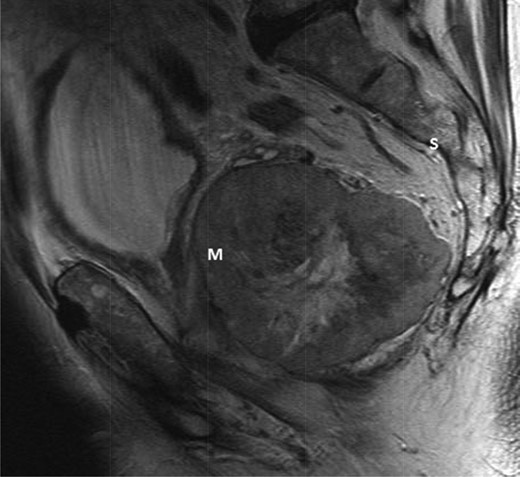

The multidisciplinary team review advised neoadjuvant treatment with imatinib mesylate and further reassessment. Repeat MR pelvis and staging PET CT abdomen, thorax and pelvis were then performed. These showed a large extra-luminal tumour with downsizing in tumour bulk (6 × 5.7 × 5.4 cm) (Figs 3–5) but in close approximation with the right seminal vesicle.

T2-weighted sagittal images after 3 months of imatinib mesylate therapy. The mass has shown a significant reduction in size (Mass = m, Sacrum = s).